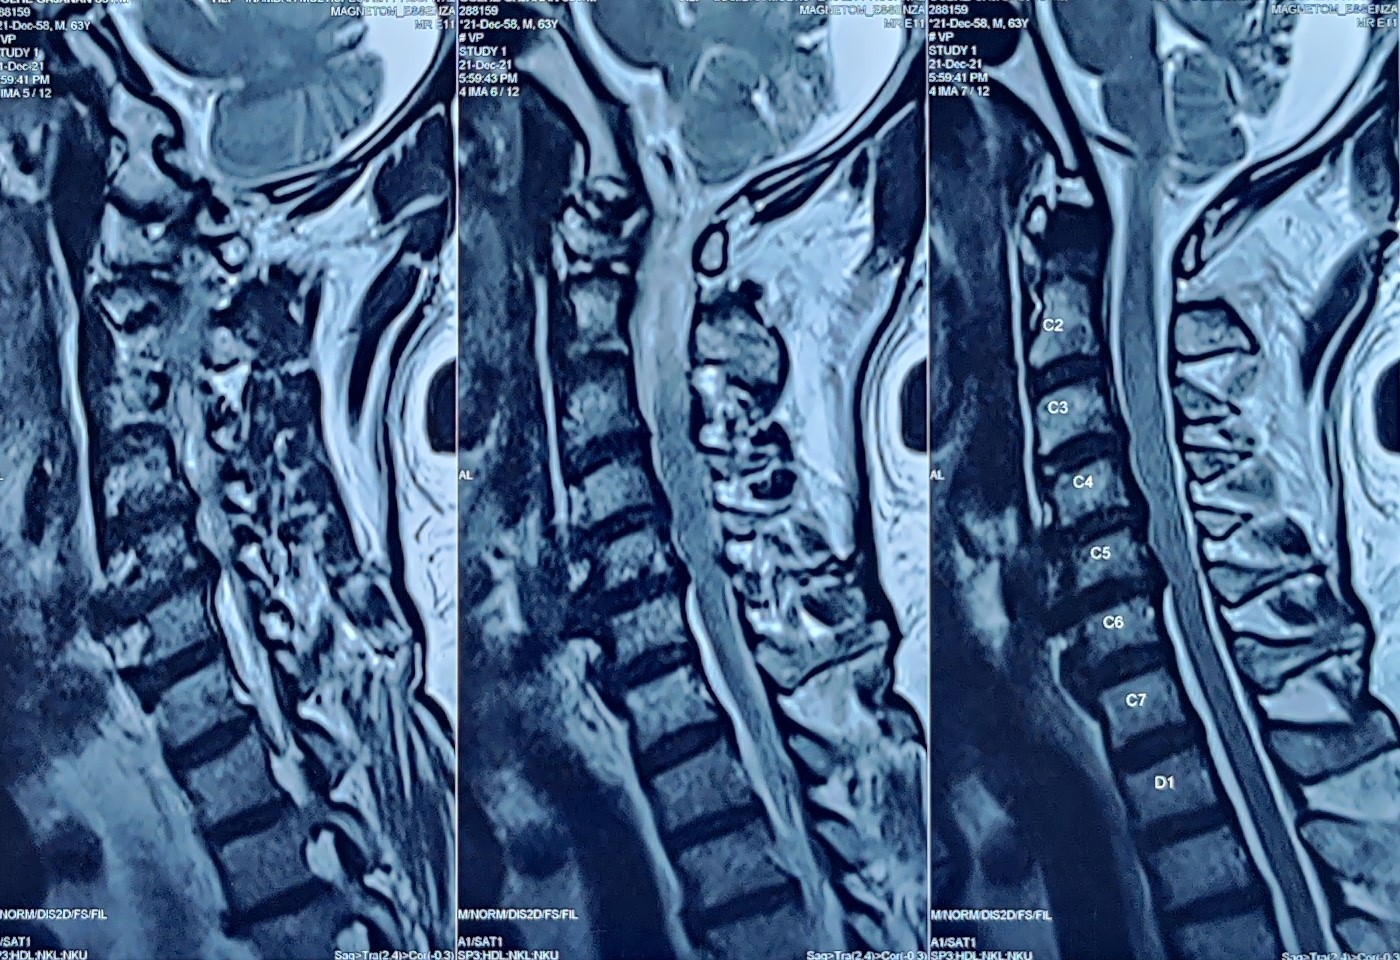

• Prolapsed Intervertebral disc disease in cervical region

• Chronic neck pain with multiple level disc disease

• Spinal stenosis with radicular pain

Most patients need only one injection, however, some patients with big disc may need repetition of the procedure. Decision to repeat the procedure is taken by your doctor looking at your MRI and the relief percentage from previous procedure.